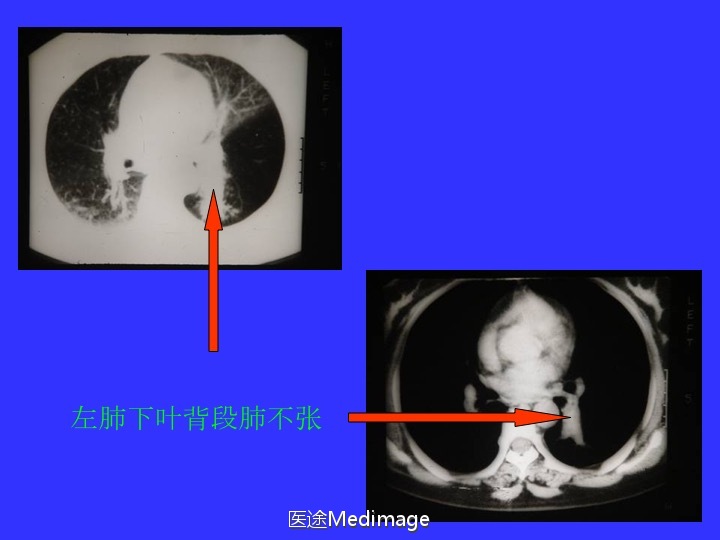

胸部CT阅读与诊断(三)各种肺不张